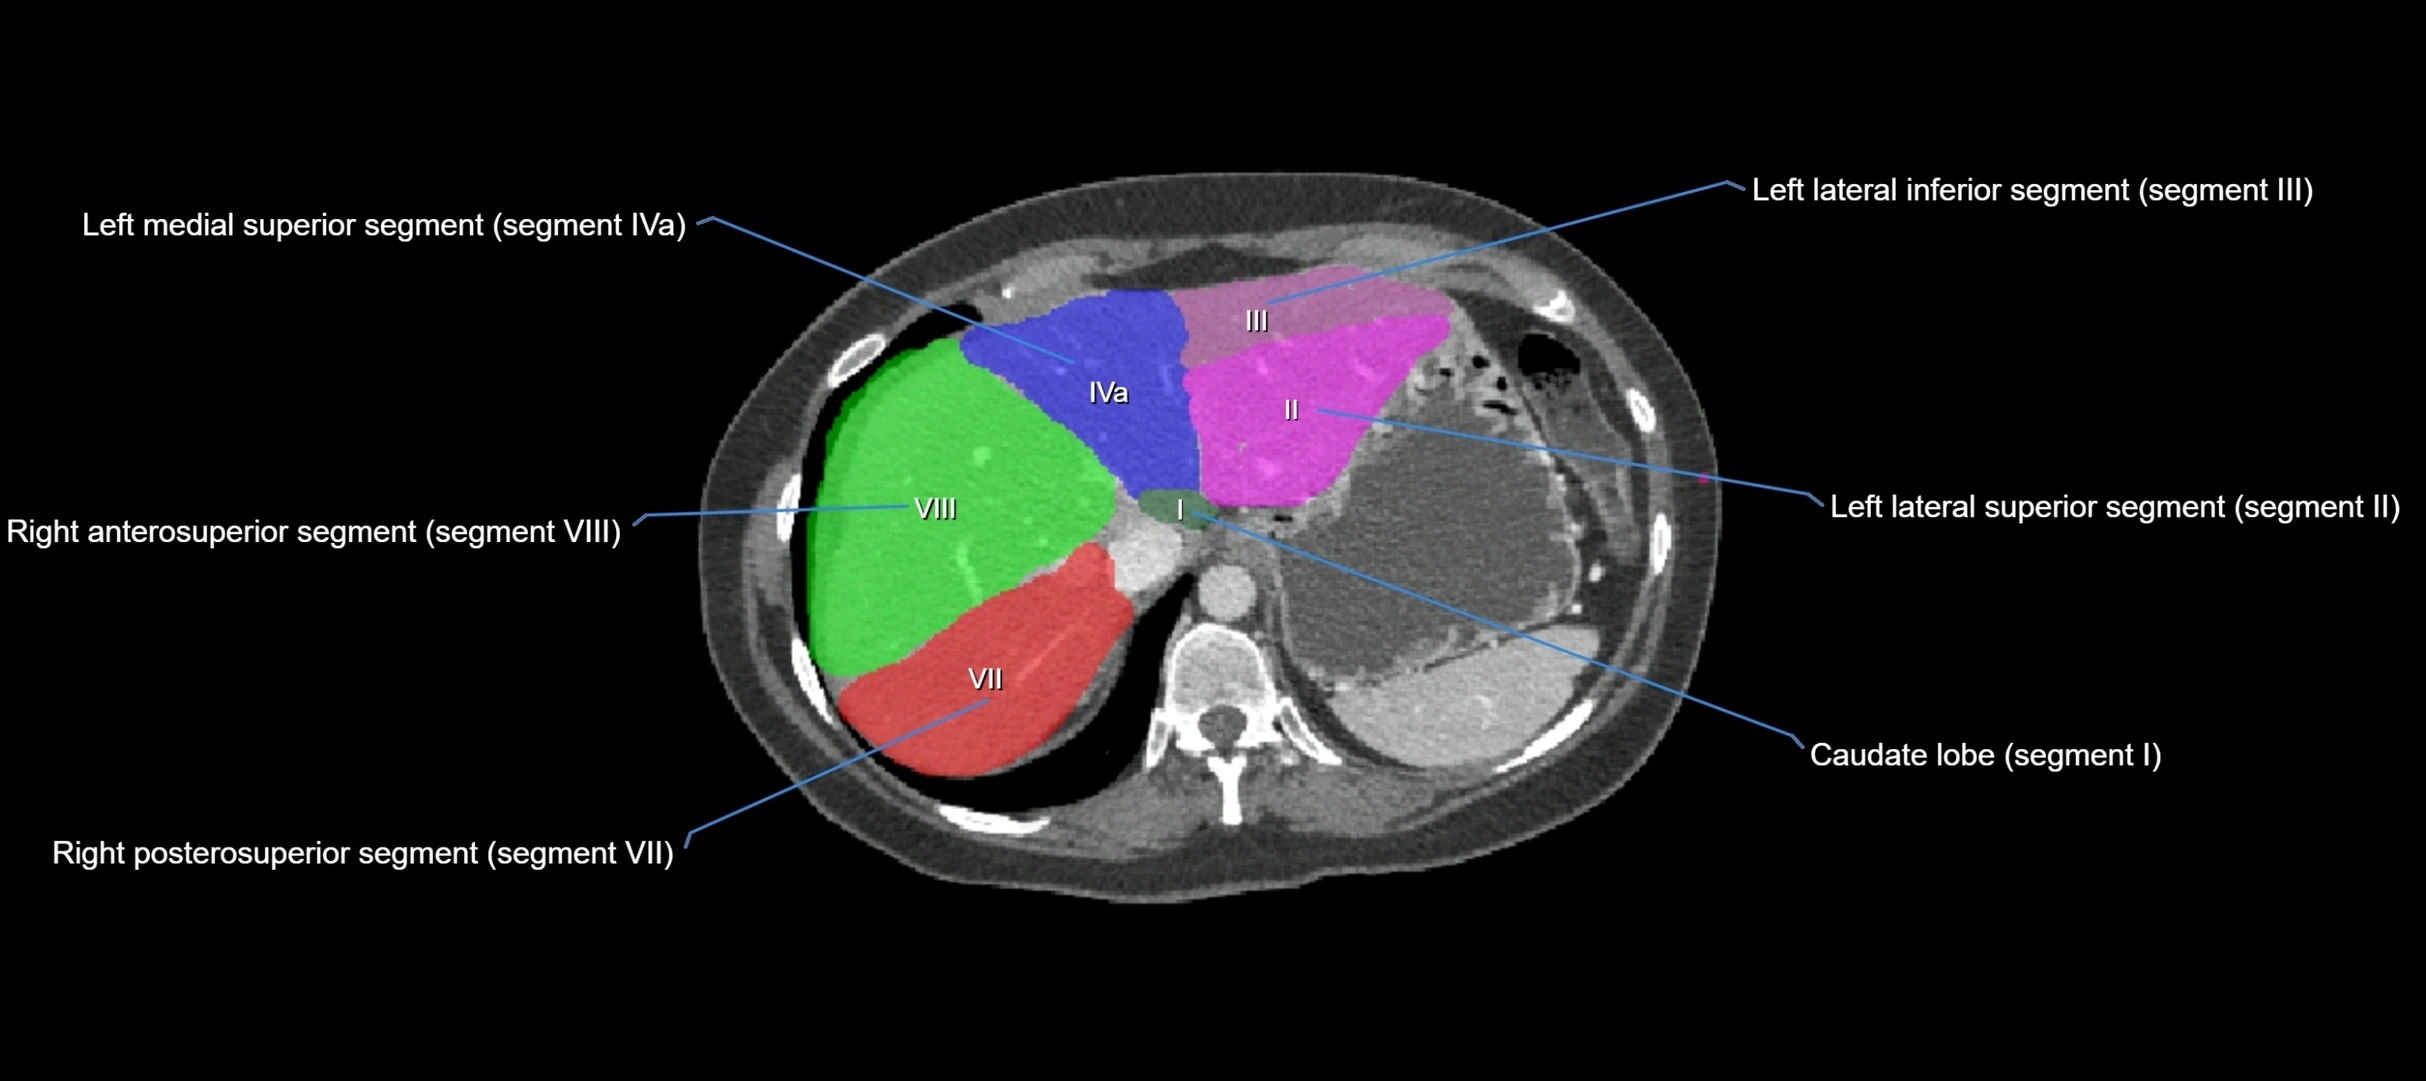

CT Image

image